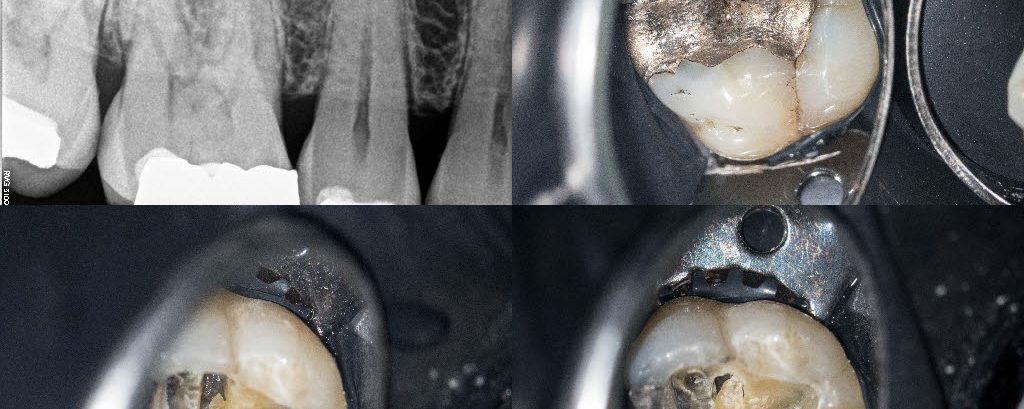

Pulp stones

Necrotic/SAP. Pulp stone sectioning and removal using US, interim CaOH till resolution of symptoms. 4 canals and resin core, tried Bioclear matrices. Crack noted on the mesial aspect, no significant probing.  Advised a crown.